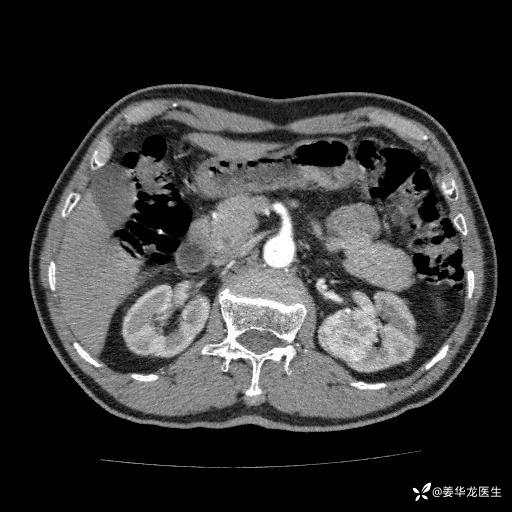

左肾中心型肾门部肿瘤39mm×34mm×36mm,右肾GFR25ml/min,部分切还是全切?

患者75岁老年男性,体重50kg,无高血压、肾病、糖尿病等基础病,检查发现左肾中心型肾门部肿瘤,右肾GFR只有25ml,无肉眼血尿,无镜下血尿。入院验血常规检查均正常,包括肾功能,肌酐102.7umol/L.

二、左肾肿瘤与左肾集合系、左肾动静脉关系密切,左肾部分切除术可行吗?成功率有多大?成功部分切后,肾功能还有多少?

四、左肾根治疗切除术后,透析的机率有多大?